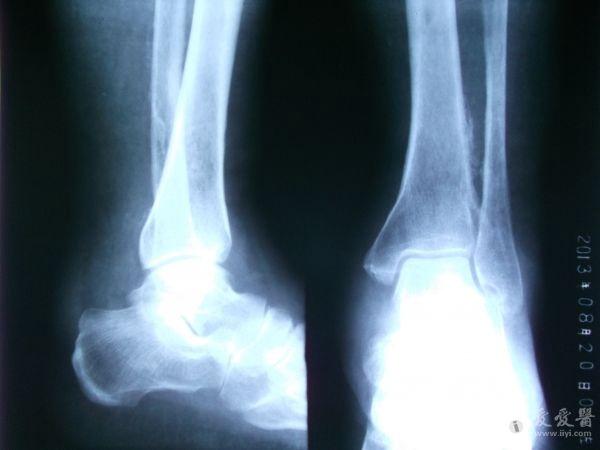

男性,56岁,左小腿静脉曲张十多年了吧,好像做过手术。现在他的整条左小腿肿胀,皮肤发黑,靠近外踝的皮肤出现溃疡。片子不太清楚,因为是基层,条件艰苦没CR。请各位前辈指点下,该患者的左胫、腓骨是什么状况,应该怎样发报告?谢谢!

患者有静脉曲张的病史,现在小腿的肌肉和皮肤都出现缺血坏死的症状;而胫腓骨X光片示胫腓骨下段向对面骨皮质增生模糊,有明显的骨膜反应;也还是考虑骨质长期缺血缺氧所致,类似肺癌所致骨皮质增生的改变。当然,骨髓炎和骨肉瘤等来源骨质本身的疾病不能完全排除。

胫腓骨下段骨皮质模糊,出现葱皮样骨膜反应,骨髓腔稍狭窄,软组织情况不清。考虑急性骨髓炎可能,为排除骨肉瘤,建议CT。